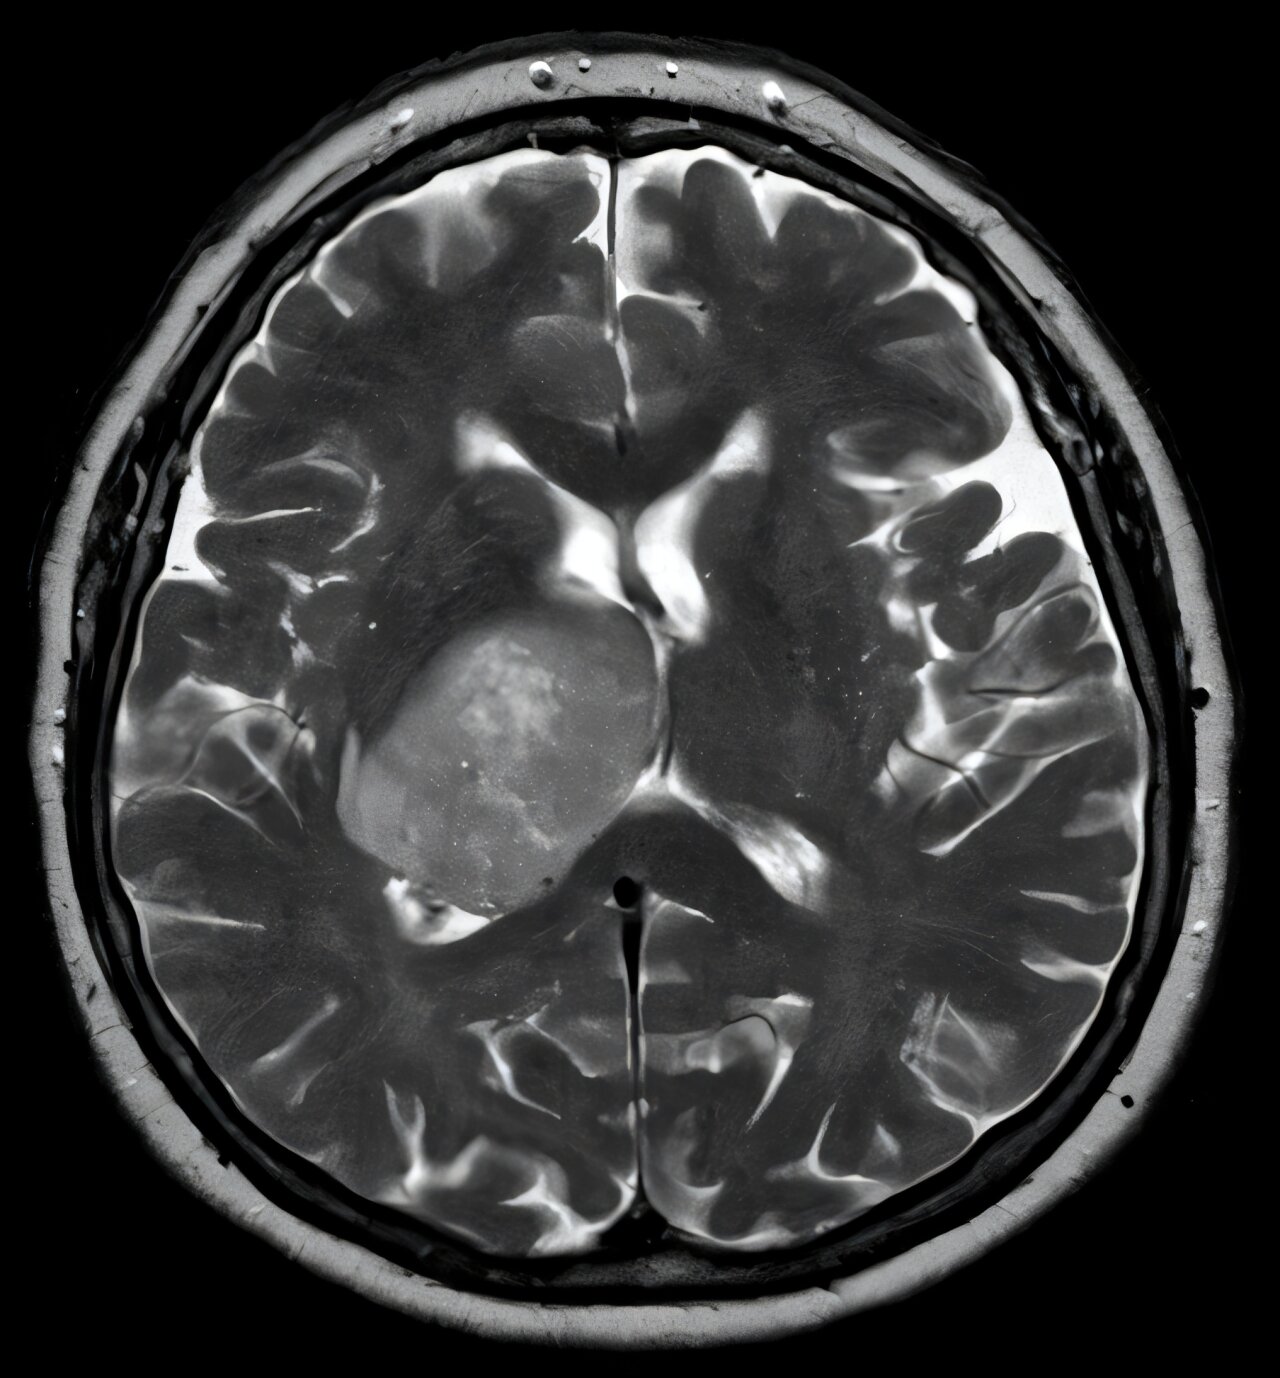

AI distinguishes glioblastoma from look-alike cancers during surgery

The Harvard Medical School-led research team has developed an AI tool that can explain separate origin, behavior and treatment in addition to two look-alik cancer found in the brain.